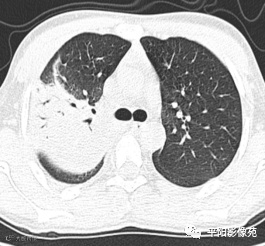

入院CT:

影像特征:X线片右肺中上野片状高密度影,下缘以叶间裂为界,上缘及外侧缘模糊;CT位于右肺上叶后段,呈片状实变影,内见支气管影,边缘模糊。

影像诊断:右肺上叶大叶性肺炎。